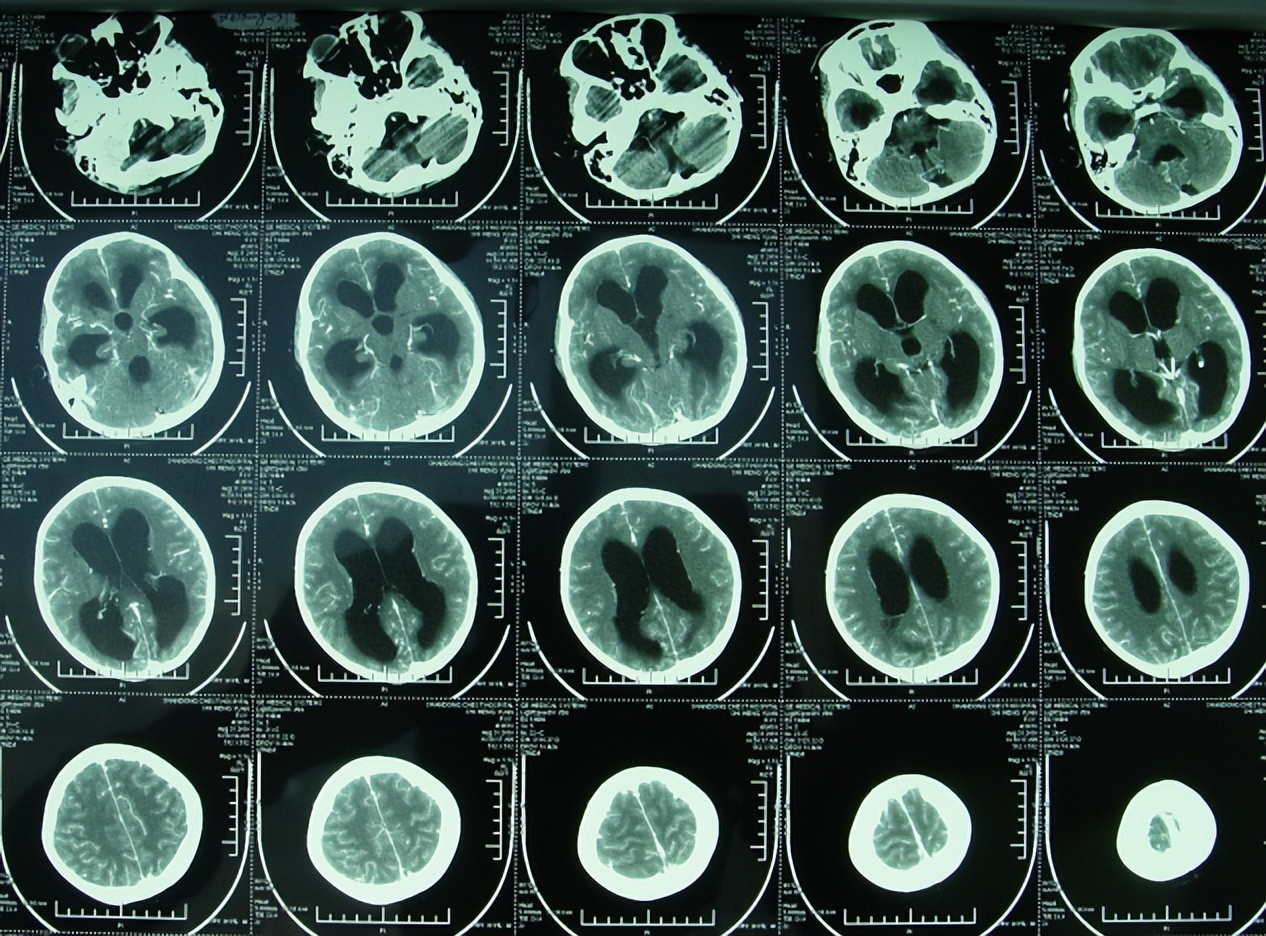

入院时CT检查发现在持续腰大池引流情况下仍具有严重的第四脑室及其脑室系统普遍扩大的严重脑积水表现(图-11);当天给予拔出了腰大池引流管+脑室外引流术。

图-11:2010年11月29日

2010年12月2日(住院治疗3天),查头颅CT示脑室缩小(图-13)。

图-13:2010年12月2日头颅CT

2010年12月9日(住院治疗10天),查头颅CT示脑积水进一步变好(图-15)。

图-15:2010年12月9日